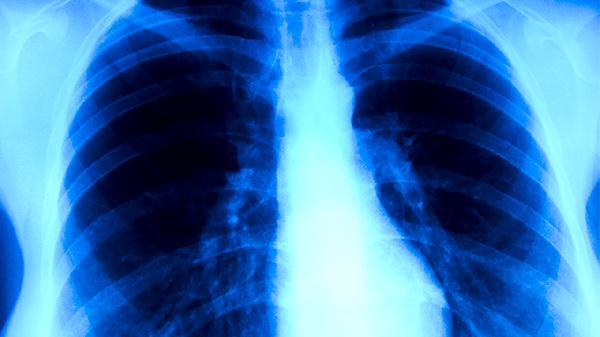

消癌平滴丸含有的活性成分可直接干扰肿瘤细胞DNA合成,阻断其有丝分裂过程。对肺癌、胃癌、肝癌等实体瘤具有显著抑制作用,能缩小肿瘤体积。使用期间需定期复查影像学检查评估疗效。常见不良反应包括轻度胃肠不适,一般不影响继续用药。